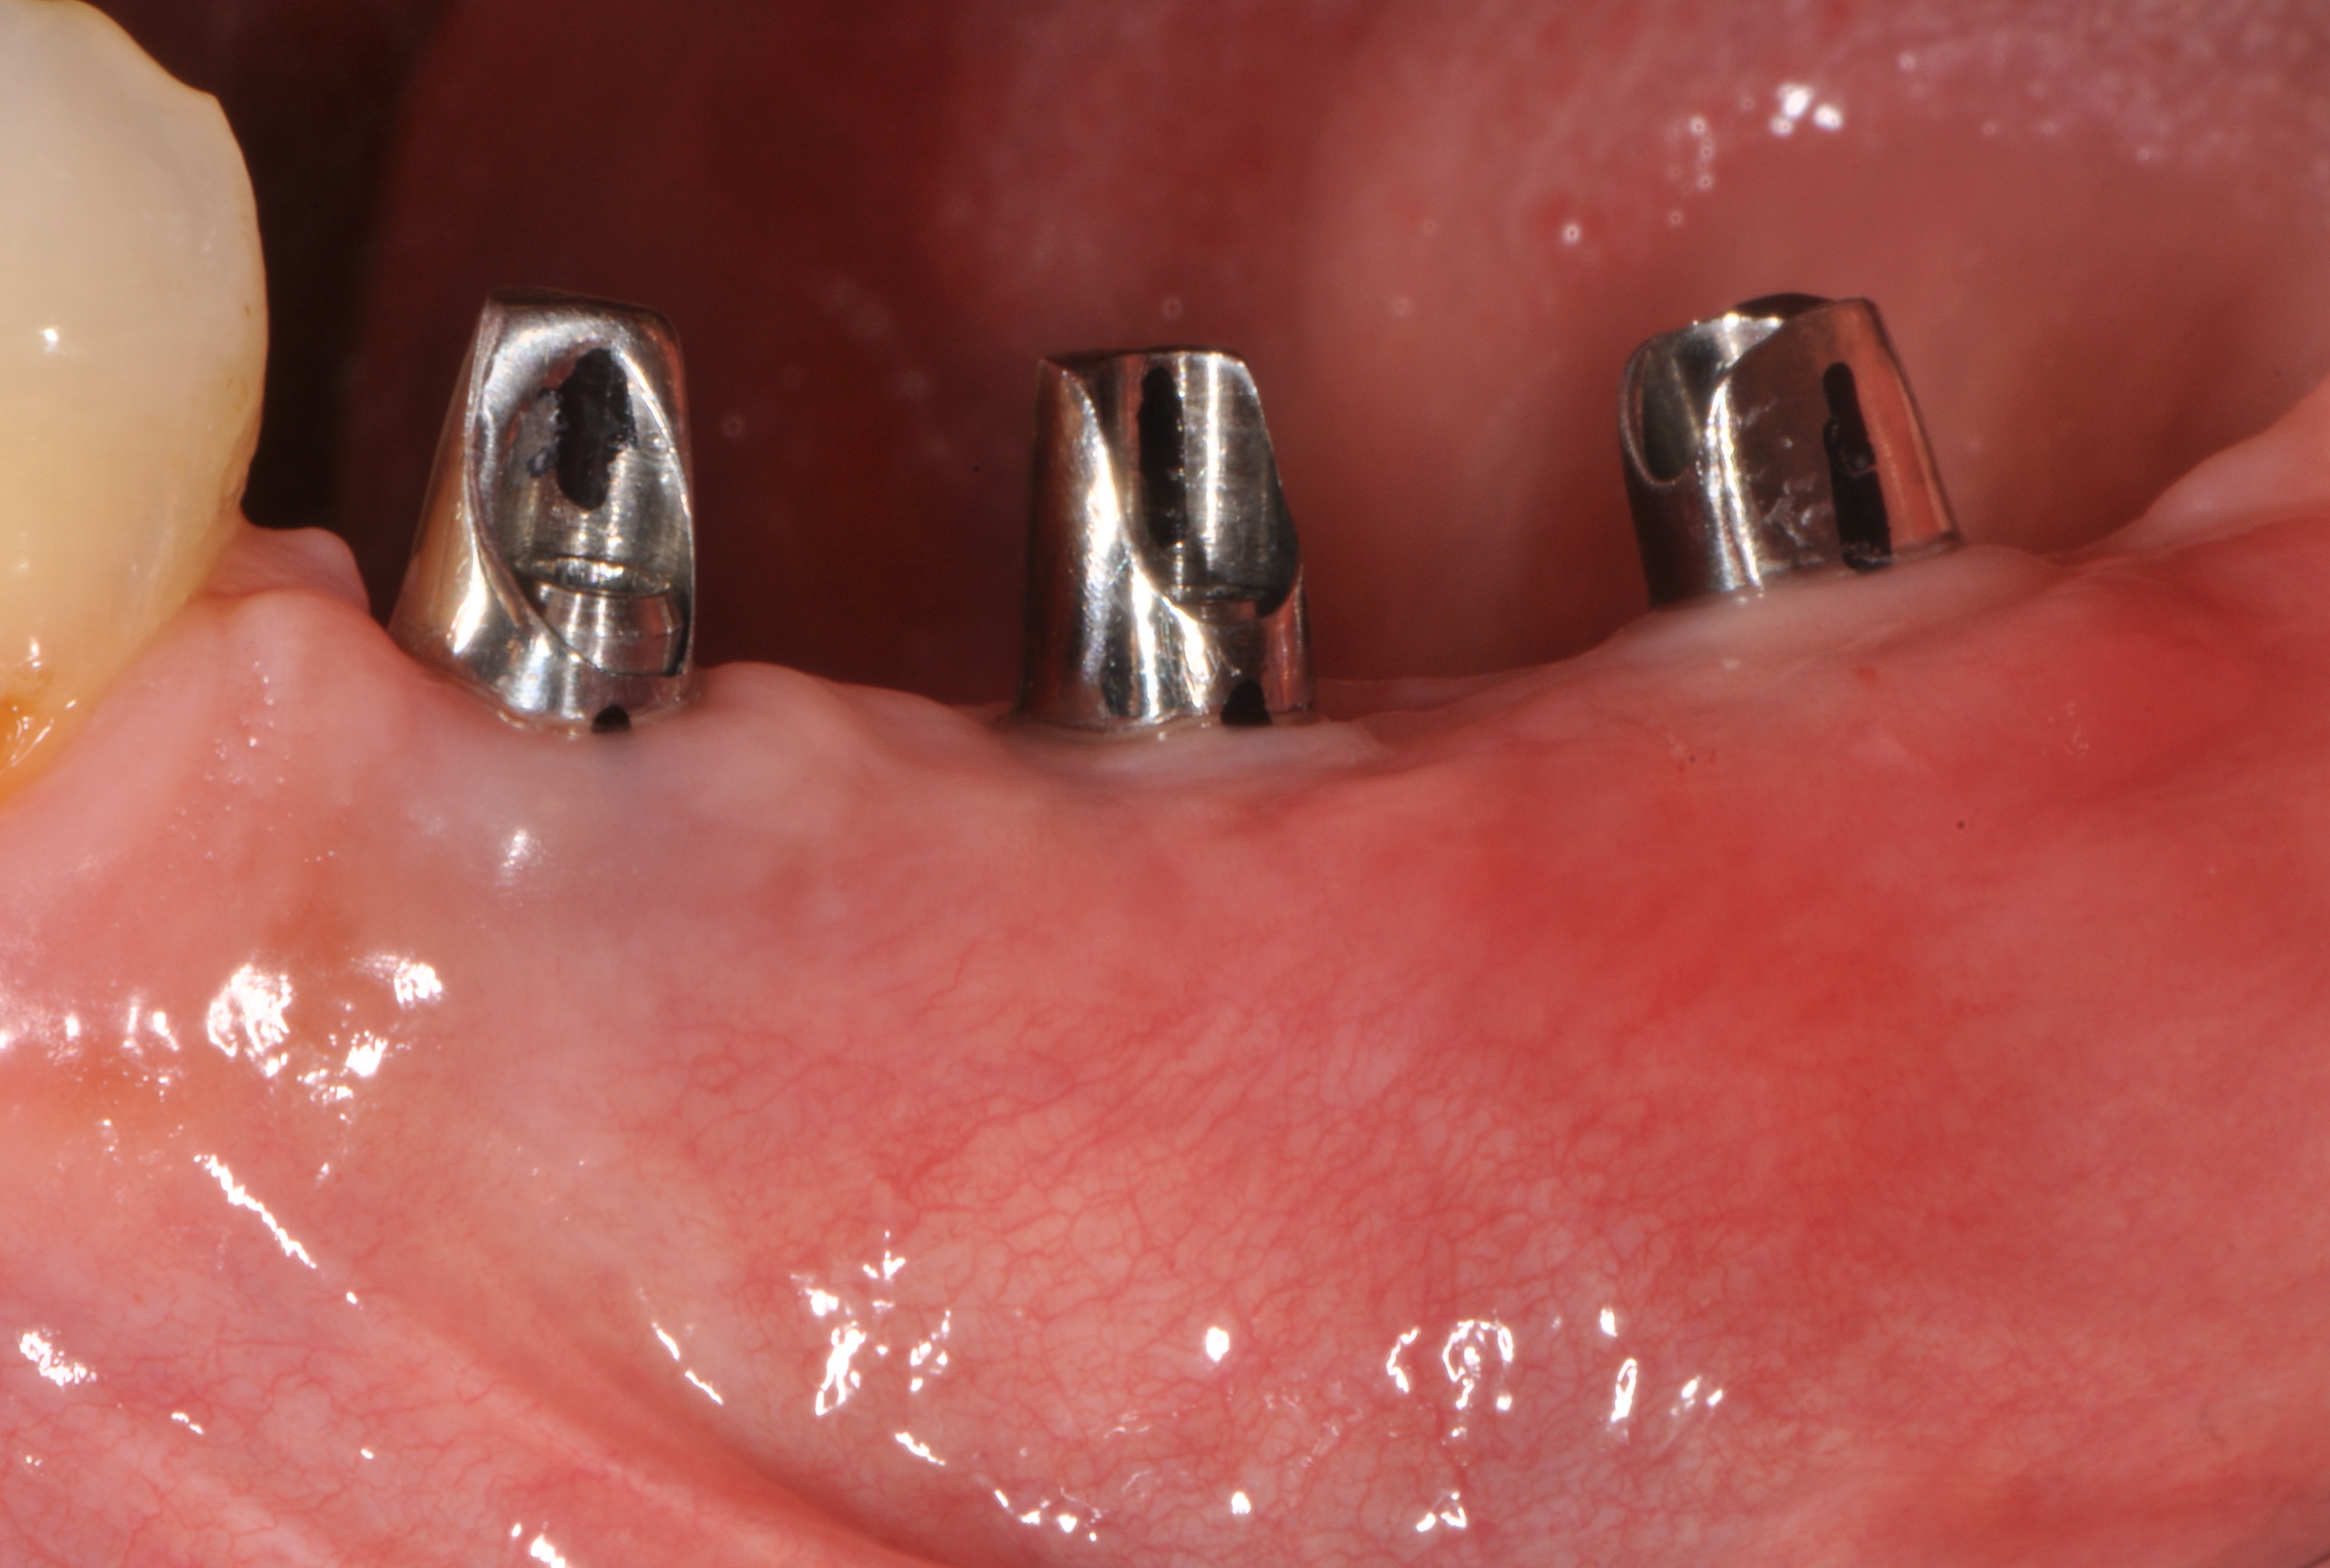

Replacement of a fixed partial denture with three implants

A 52-year-old patient is a referral and has been wearing an immediate provisional partial denture after replacement of her worn and fractured fixed partial denture. As a definitive treatment solution, the patient desired "beautiful and long-lasting" implant-supported single crowns. Clinically the CT-scan revealed a very narrow bone crest ("knife-edge") in the 3rd quadrant. Implant placement has been planned with a simultaneous GBR procedure.